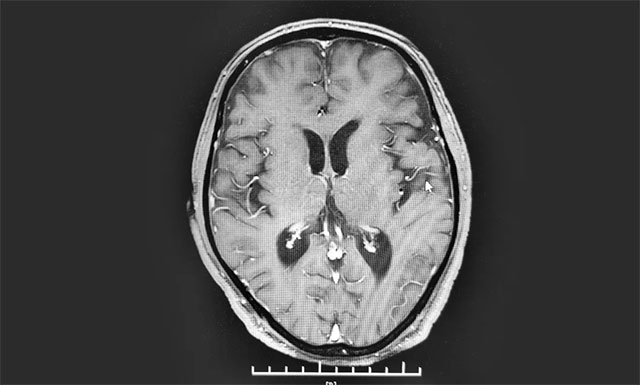

▲ 復(fù)查時(shí)病灶明顯縮小

今年8月下旬,患者經(jīng)出院休養(yǎng)后再次來院復(fù)查,病灶明顯縮小。看到復(fù)查結(jié)果,患者緊緊握住了醫(yī)生的手,感激之情溢于言表。